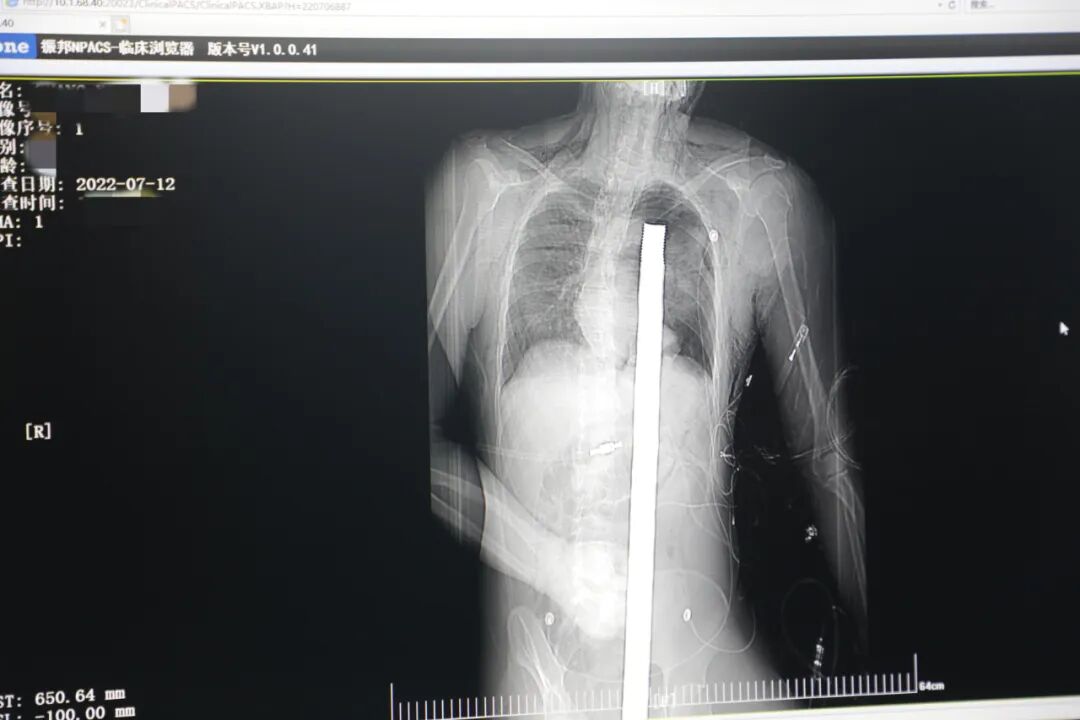

三秦都市報—三秦網(wǎng)訊(通訊員 王坤 記者 阮班慧)7月12日16時10分,西安一處工地的一名工人,不慎從10多米的高空墜落,不幸的是工地上一根直徑3厘米的螺紋鋼從男子會陰部垂直穿入體內,工友們小心翼翼地將鋼筋截斷,立即將這位身體里插著一截長120cm直徑3cm鋼筋的受傷同事緊急送往西安國際醫(yī)學中心醫(yī)院急救中心,當時正是下午17時。

時間就是生命!此時,西安國際醫(yī)學中心醫(yī)院展開了一場與生命賽跑的搶救,第一時間開辟綠色通道,急診X光片及CT顯示:異物經(jīng)會陰部貫穿盆腔、腹腔到達左側胸腔主動脈弓水平。醫(yī)院創(chuàng)傷中心立即啟動應急預案,劉延彤副院長親臨指揮,下午17點48分,當患者被送達手術室,胸外、心外、肝膽外科、胃腸外科,泌尿外科及麻醉科等多學科專家聯(lián)手對這名工人進行“縱劈胸骨+前外側開胸探查+氣管及主支氣管修補+肺修補+血胸清除+開腹探查止血+腹膜后及盆腔探查”手術

情況緊急!術中探查后發(fā)現(xiàn),長120cm直徑3cm的螺紋鋼經(jīng)患者右側會陰部穿入,傷及直腸,途徑膀胱后方,左側髂總動靜脈之間傷及左腎后,經(jīng)胰腺后方在肝脾之間穿破膈肌,在下肺靜脈前方穿入左肺穿破氣管及左右主支氣管膜部,止于主動脈弓下水平,穿入體內的部分達到75cm。